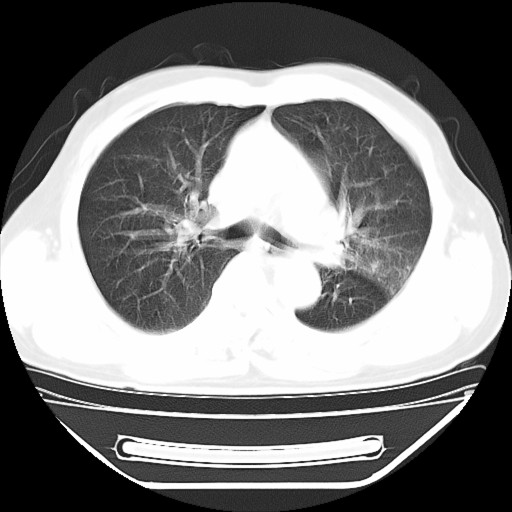

以下是引用hhcckk在2009-5-29 10:34:00的发言:[br]左下肺片絮状边缘模糊影,考虑感染,建议治疗后复查[br]